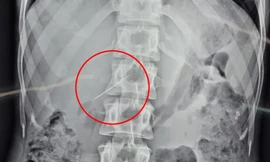

TPO - Trong quá trình phẫu thuật, các bác sĩ phát hiện ổ áp xe lớn, đường kính hơn 10 cm, nằm ở thùy gan trái và dính vào bờ cong nhỏ của dạ dày. Bên trong, có một chiếc tăm tre dài khoảng 5 cm đã cắm sâu vào nhu mô gan.